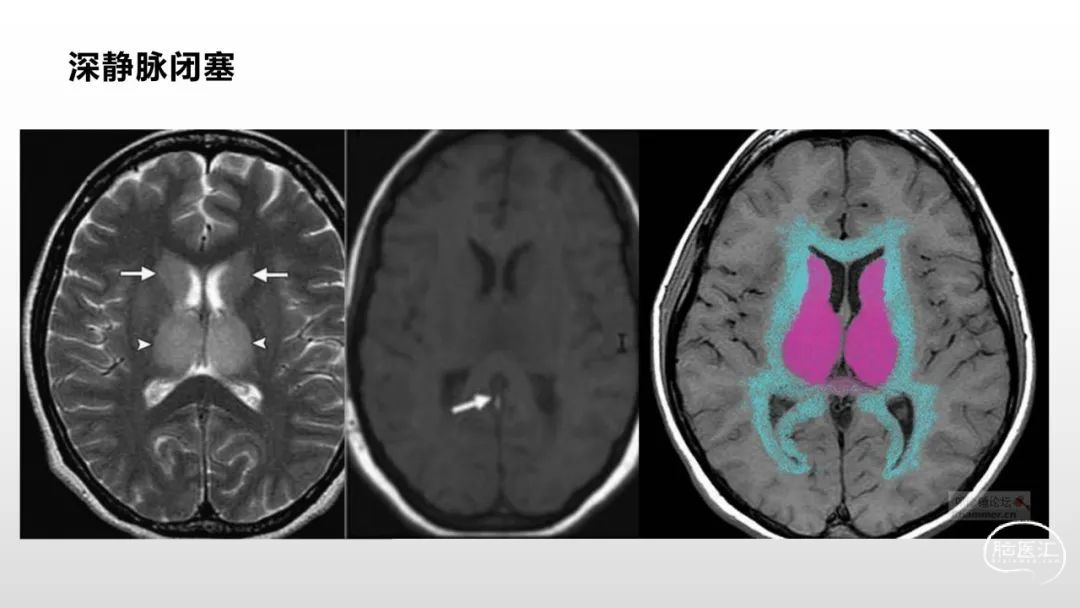

颅脑影像诊断基础知识讲座:感染和免疫性疾病1